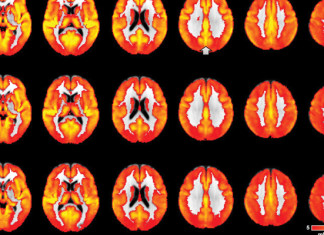

Científicos descubren posible causa de la enfermedad de Alzheimer en el...

Si bien existe una creciente evidencia de que el sistema inmunitario está implicado en la enfermedad de Alzheimer, no está claro cómo. Ahora un...

En los ratones con Alzheimer, memoria restaurada con medicamento contra el...

La memoria así como las conexiones entre las células cerebrales se restauraron en ratones con un modelo de un determinado medicamento experimental contra el...